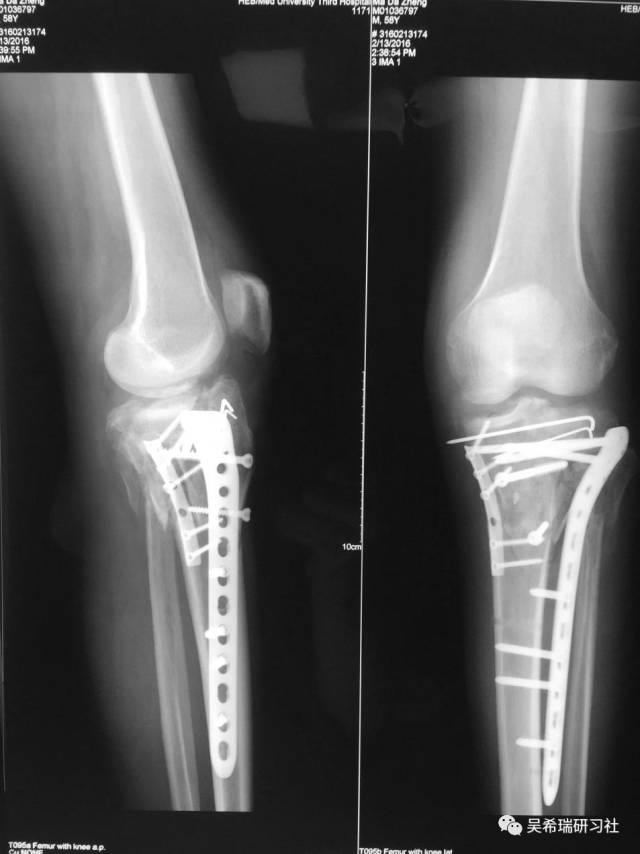

病例3

平台骨折手术后继发感染

TIPS:内固定感染常见病不要轻易做皮瓣,感染情况下不可深部骨感染、窦道用水泥切实可行多数皮肤没有缺损,肿胀消退后可以牵张闭合